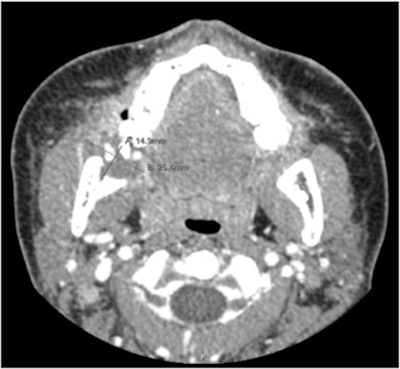

Upon admission, the patient underwent a CTA with intravenous contrast of the maxillofacial complex. The imaging revealed a peripherally enhanced collection of fluid measuring 1.5 × 2.5 cm around the buccal and lingual surfaces of the mandibular body. Also, there was cortical erosion of the medial surface of the right mandibular ramus and vascular blushing of the inferior alveolar artery.

At this point, clinicians consulted with interventional imaging specialists who performed an angiography of her right external carotid artery under general anesthesia, according to the report.

The imaging showed contrast extravasation and a pseudoaneurysm emerging from her inferior alveolar branch of the right internal maxillary artery.